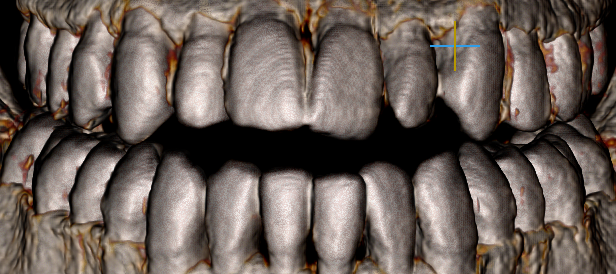

my upper palate is 37mm, is it narrow?

Should I wear marpe or something like that?